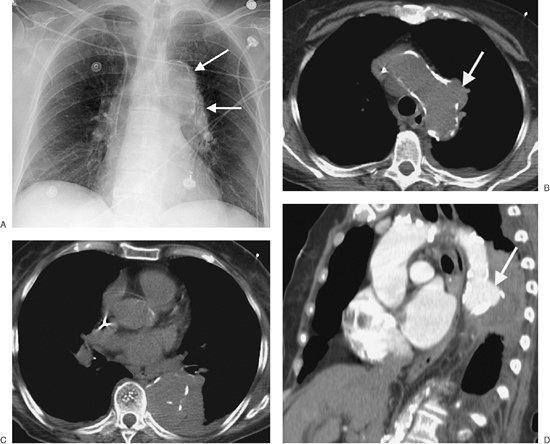

FIGURE 6-27. Leaking thoracic aortic aneurysm. A: PA chest radiograph of a 77-year-old man with chest pain shows a widened mediastinum and abnormal left mediastinal contour (arrows). B: CT scan shows a focal aneurysm of the aortic arch (arrow). Note the interruption in dense mural calcification. C: CT scan at a more inferior level shows obliteration of the normal aortic contours and adjacent left pleural effusion. D: Sagittal reformatted CT scan shows the focal aneurysm (arrow) and adjacent fluid collection.